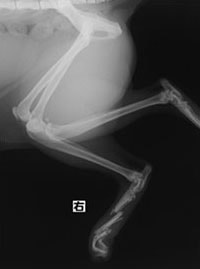

症例3:キルシュナーワイヤーのピンニングによる整復

ペルシャ猫 11ヶ月齢 雄

他院にて左大腿骨遠位の成長板骨折(salter-harrisⅠ型)が認められており、治療相談を目的として来院。当院にて、キルシュナーワイヤーを用いたピンニングにより骨折部位の整復を行いました。術後の経過は良好で、現在も経過観察中です。

術前レントゲン

術後レントゲン

機器

Arthrex社のターゲティングデバイスを用いてピンニングの位置を調整することで、確実な固定を行っています。当院ではこの手術器具以外にも、人の手術にも使用される様々な器具を導入し、手術精度を高め、また医療メーカーと新しい器具の開発、試作にも取り組んでおります。